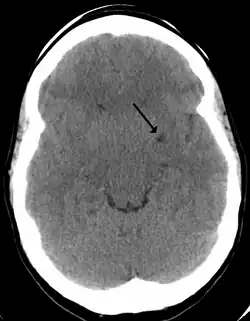

Dilated perivascular spaces are categorized into three types:[7]

- Type 1 are located on the lenticulostriate arteries projecting into the basal ganglia

- Type 2 are located in the cortex following the path of the medullary arteries

- Type 3 are located in the midbrain

Perivascular spaces are most commonly located in the basal ganglia and white matter of the cerebrum, and along the optic tract.[13] The ideal method used to visualize perivascular spaces is T2-weighted MRI. The MR images of other neurological disorders can be similar to those of the dilated spaces. These disorders are:[7]

Perivascular spaces are distinguished on an MRI by several key features. The spaces appear as distinct round or oval entities with a signal intensity visually equivalent to that of cerebrospinal fluid in the subarachnoid space.[7][14][15] In addition, a perivascular space has no mass effect and is located along the blood vessel around which it forms.[14]